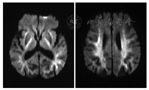

图2

早产儿脑室旁出血和后期白质软化、侧脑室扩张 A:纠正胎龄35周时;B:2岁时

Figure 2

Periventricular hemorrhage and late white matter softening and la-teral ventricular dilatation in premature infants A:at 35 weeks postmenstrual age;B:magnetic resonance imaging at 2 years old